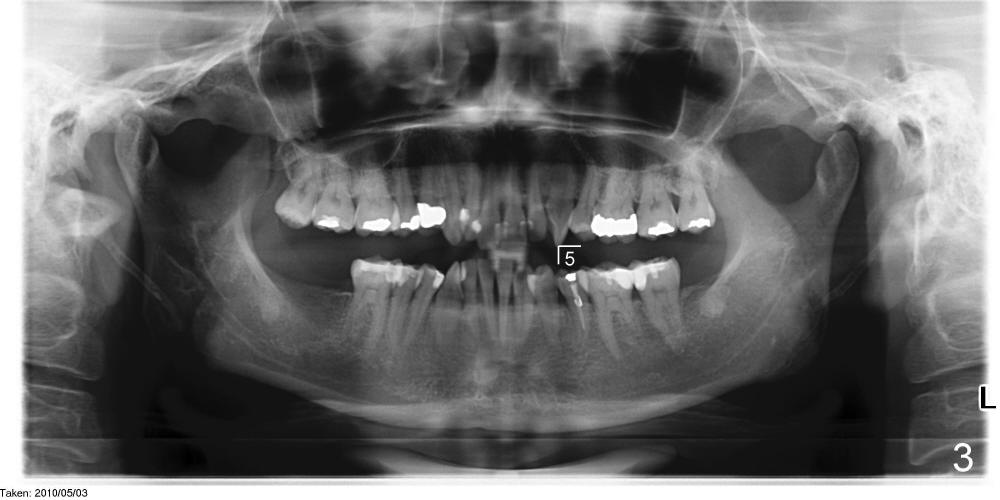

言归正传,五十一岁女人昨天第一次来诊所就诊(急诊),去年十一月在别的诊所右下第一双尖牙远中做树脂修复,术中发现穿髓,术后不时,现在颊侧根尖有压痛,根尖片显示根尖阴影(图一),多谢田智敏几天前指导,现在看根尖片,多注意些根尖弯曲,根管治疗中,不由自主地事先弯曲细小根管锉(hand files),一点没有问题,一直使用到二十号根管锉,根管长度21.5毫米(working length (WL)),下颌第一双尖牙一般单根,属于大根(方老师见解),接着用40/.06 rotary file(用了几年rotary files,大多数根管治疗好像不需要按部就班地使用crown down 技术:例如先用40/.10 rotary file,然后40/.08, 再用40/.06),问题在于这个rotary file只能进入十七毫米,突然在梦中清醒:根管是弯曲的。由于急诊时间紧,接着使用30/.04 rotary file,能达到WL,然后让漂白液浸泡根管十到二十分钟,去处理另外一个病人。回来后用30/.06 rotary file也没有问题,反复冲洗后,吸干根管,放置Ca(OH)2糊剂(图二:超冲些)。如果下次病人回来时没有疼痛症状,冲洗掉Ca(OH)2糊剂,便使用30/.06主牙胶尖充填,重新做树脂修复(老的有leakage),如果新的树脂没有leakage(拍摄X光片),我可能同意病人意见:不做牙冠。仿佛这例牙冠必要性不大。方老师,田兄,或者任何人:您们怎么处理这样病例?图三是以前拍摄的全景片,显示左下第二双尖牙根尖够弯曲的。